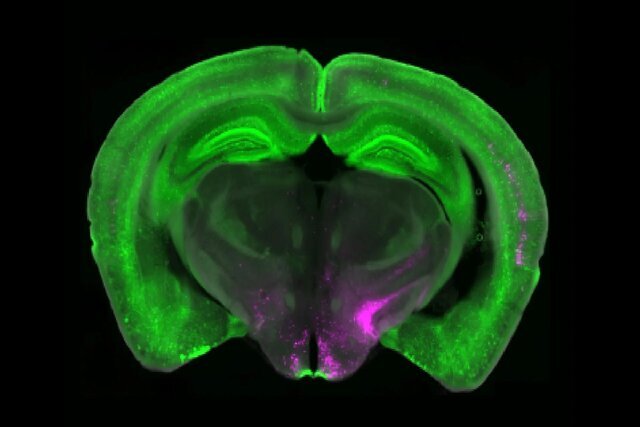

بتلی به همراه پژوهشگران «دانشگاه پیتسبرگ»(University of Pittsburgh)  و «موسسه پژوهشی اسکریپس»(Scripps Research Institute)، قطعه مهمی را از پازل درد مزمن کشف کرده‌اند. تحقیقات آنها به گروه خاصی از سلول‌های بنیادین مغز به نام «نورون‌های بیان‌کننده گیرنده»(Y۱R)  اشاره دارد که در «هسته پارابراکیال»(Parabrachial nucleus)  مغز قرار گرفته‌اند. این نورون‌ها در حالت‌های درد مداوم فعال می‌شوند، اما سیگنال‌های مربوط به گرسنگی، ترس و تشنگی را نیز پردازش می‌کنند. این نشان می‌دهد که مغز می‌تواند واکنش به درد را در زمان نیازهای فوری‌تر تنظیم کند.